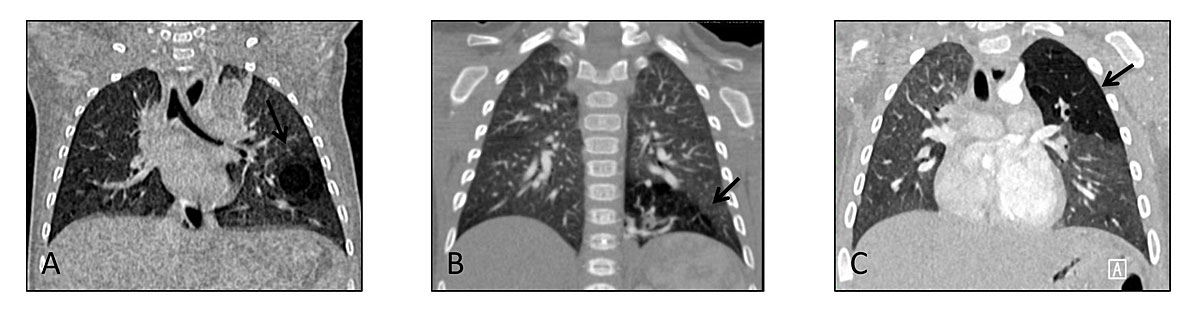

Finally, congenital anatomical lung anomalies are a continuum of lung malformations that depend on factors such as foregut, vascularisation, pulmonary parenchyma or airway components, and that are all related to abnormal embryological development (fig. 2) [1]. In the spectrum of these rare malformations, the most frequent are: congenital pulmonary airway malformations (CPAMs) (previously named congenital cystic adenomatoid malformations, CCAM) (fig. 3A); bronchopulmonary sequestrations (fig 3B); and congenital lobar or segmental hyperinflation (previously named emphysema) (fig 3C) [2]. As a result of ongoing improvements in ultrasound technology, these malformations are often diagnosed prenatally and 80% of them are asymptomatic at birth [3]. The CPAM classification described by Stocker includes five different types of focal lesion (0 to 4) [1], based on a macroscopic anatomical description of the lesion and a histological description of the cells with haematoxylin and eosin staining after surgical resection [4]. The CPAM types are differentiated by the size of the cystic lesion and cell types present in the cystic lesion (columnar, cuboidal or ciliated). However, this phenotype description is not of much help in patient management, except for detecting a possible diagnosis of malignant transformation. From a research perspective, the pathophysiological mechanisms leading to CPAM remain unclear. Dysregulation of several genes that modify cell proliferation and/or apoptosis has been suggested [5]. Interestingly, even if congenital lung diseases can often be linked to genetic mutations, congenital lung anomalies often lack a known genetic footprint [6, 7]. In the majority, Mendelian transmissions are not present and localised malformations are most likely related to defects in cellular interaction during lung formation [8].

Figure 3 Thoracic computed tomography (CT) scans of paediatric patients with congenital lung anomalies. Coronal cuts of thoracic CT scans performed between the ages of 4 and 6 months. Black arrows point at the lesion on each picture. A. Congenital pulmonary airway malformation. B. Bronchopulmonary sequestration. C. Congenital lobar segmental emphysema.